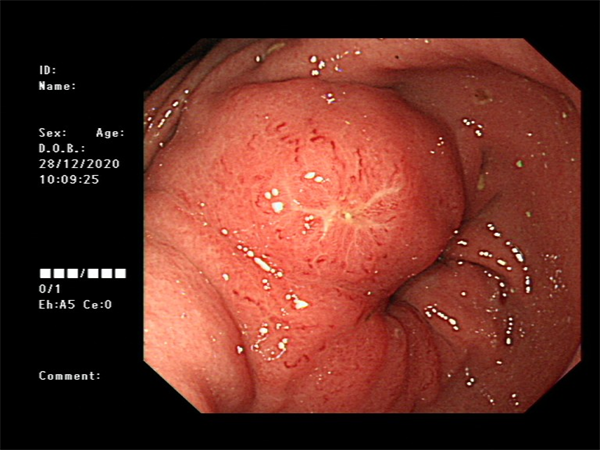

患者周某,男60岁,体检行肠镜发现直肠肿物,行肠镜下直肠黏膜下剥离术(ESD),术后病理:绒毛状管状腺瘤,局灶呈高级别上皮内瘤变。

· 消化道息肉切除术

· 食管、胃、结直肠早期癌粘膜下剥离术(ESD)